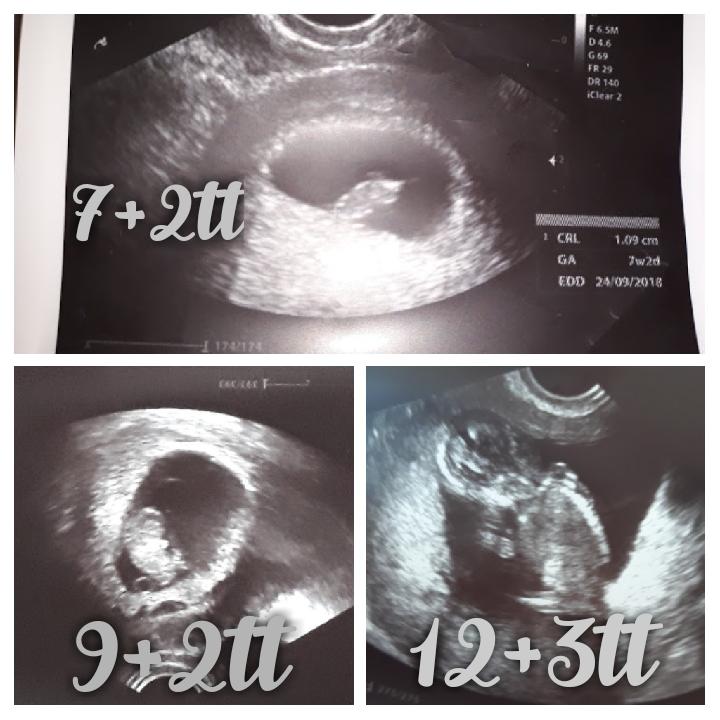

jeej vidim ze mas novu foto 😉 kolko meria babatko?

@xarin ďakujem ano dnes poradna 🙂 ...meria 5,6cm 🙂